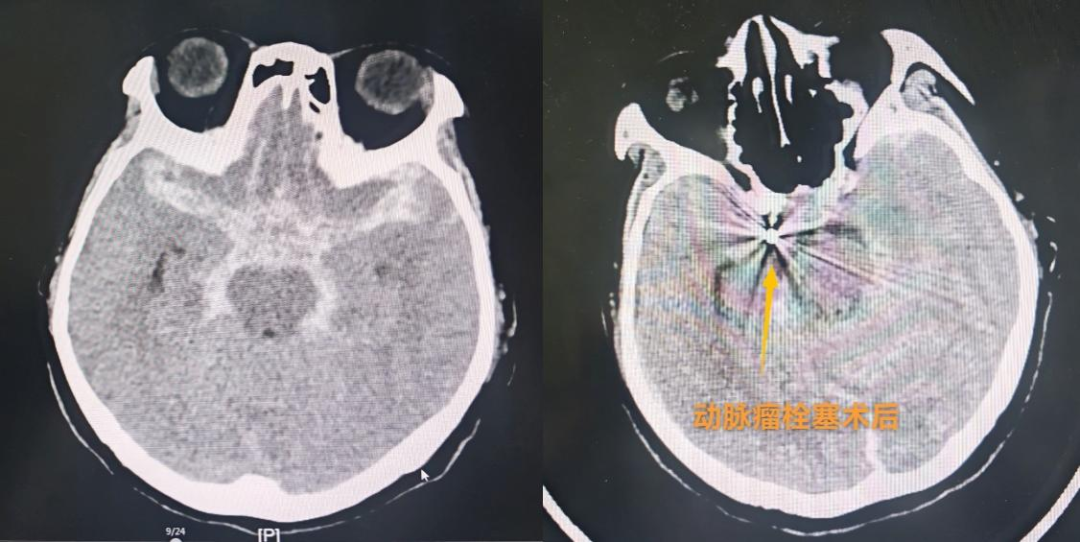

随后,关键的栓塞术开始。治疗团队通过患者大腿根部的股动脉穿刺,将纤细的微导管在X线透视引导下,最终准确送达颅内动脉瘤腔内。通过微导管,将柔软的可解脱弹簧圈填入动脉瘤囊内,直至将其完全致密填塞,血流不再进入瘤腔,从而彻底消除了再次破裂出血的风险。整个手术过程要求术者具备规范的导管操控技术和丰富的经验。团队凭借默契的配合和精湛的技术,成功完成了栓塞,术后造影显示动脉瘤完全不显影,载瘤动脉通畅,手术取得圆满成功。